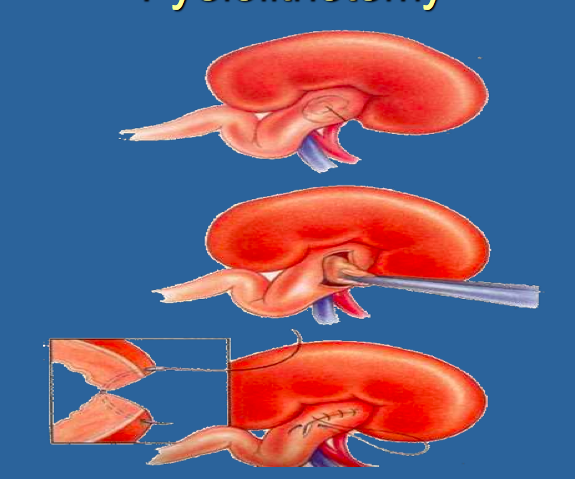

Surgery for Nephrolithiasis Described Below:

Can be used to Remove Calculi when Proximal Ureter and Renal Pelvis are Dilated

Pyelolithotomy

*Making an Incision into the Renal Pelvis to Remove a Stone

*Have to have Swelling/Dilation for you to have Access to Renal Pelvis

What are Advantages of a Pyelolithotomy over a Nephrolithotomy?

Pyelolithotomy- Does NOT Require Occlusion of Blood Supply and does NOT Damage Nephrons

*Better to use Pyelolithotomy when Stones are Located in Renal Pelvic Area because it has Advantages over Nephrolithotomy